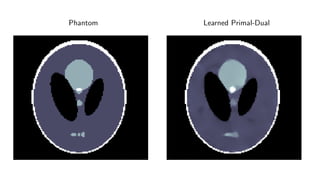

Results

ellipses

Results for ray transform inversion in 2D.

Inverse problem:

g = P(f ) + δg

Geometry: Parallel beam, sparse view (30 angles)

Noise: 5% additive Gaussian

Data: 128 × 128 pixel ellipses

Compare to:

FBP

Total Variation

Post-processing deep learning by U-Net

Phantom Training Phantom

Phantom Learned Primal-Dual

Quantitative

Method PSNR (dB) SSIM Runtime (ms) Parameters

FBP 19.75 0.597 4 1

TV 28.06 0.928 5 166 1

Learned U-Net 29.20 0.943 9 107

Learned Primal-Dual 38.28 0.988 49 2.4 · 105

Comments

Very large quantitative improvement =⇒ PSNR not good metric

Noticable visual improvement

Speedup enables clinical implementation

We are remarkably close to the theoretical optimum